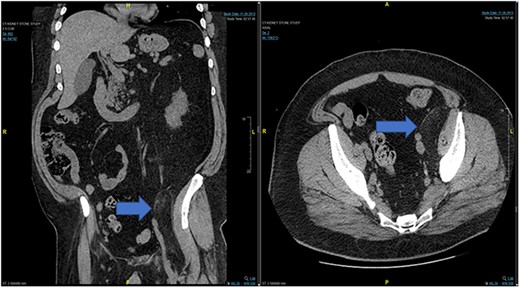

Case 1: CT (axial and coronal view), blue arrow marks hibernoma.

In the emergency department, vital signs were remarkable for elevated blood pressure of 166/81, but otherwise stable and afebrile. WBC count was elevated at 15.4 with left shift and hemoglobin was low at 9.6. Complete Metabolic Panel was notable for hyponatremia of 128, and mildly elevated BUN/serum creatinine of 26/1.5 which was slightly higher than his baseline of 17/1.3. Liver function tests were unremarkable. UA showed likely UTI with positive esterase, high RBC/WBC and bacteria and protein. A CT of the abdomen and pelvis was done, showing a left non-obstructing kidney stone and a left retroperitoneal fat density with stranding along the left iliopsoas measuring 12.6 × 8.1 cm × 3.7 cm, which was described as possibly a part of infectious or malignant process (Fig. 5). Subsequently, patient’s prior CT scans were available to be reviewed and it showed the same lipomatous mass 9 years earlier. (Fig. 6). Given the patient’s symptoms of left lower extremity pain and the possibility that the mass was responsible, a CT-guided core biopsy was ordered for diagnosis to rule out a malignant process as operative intervention was being contemplated. Pathology report of the core biopsy showed lobules of univacuolated adipocytes divided by thin septa. There were frequent multivacuolated adipocytes with small round nuclei, reminiscent of brown fat cells. No enlarged hyperchromatic cells, mitotic figures nor necrosis are seen. The findings supported the diagnosis of the lipoma variant of hibernoma (Fig. 4). Given the chronicity of the mass, the near identical size over 9 years and the diagnosis made from core biopsy, it was determined that the hibernoma was not the likely source of the patient’s LLE pain and hence the mass was not excised.